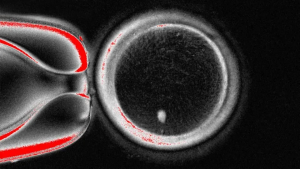

The results were striking. The team created 82 viable eggs known as OOCYTES, which were then fertilised with sperm in a lab. Nearly one in ten developed into blastocysts, a crucial stage in embryo growth that usually occurs six days after fertilisation in natural conception. While none progressed further, the very fact that human embryos were formed from skin-cell-derived eggs represents a milestone in reproductive science.